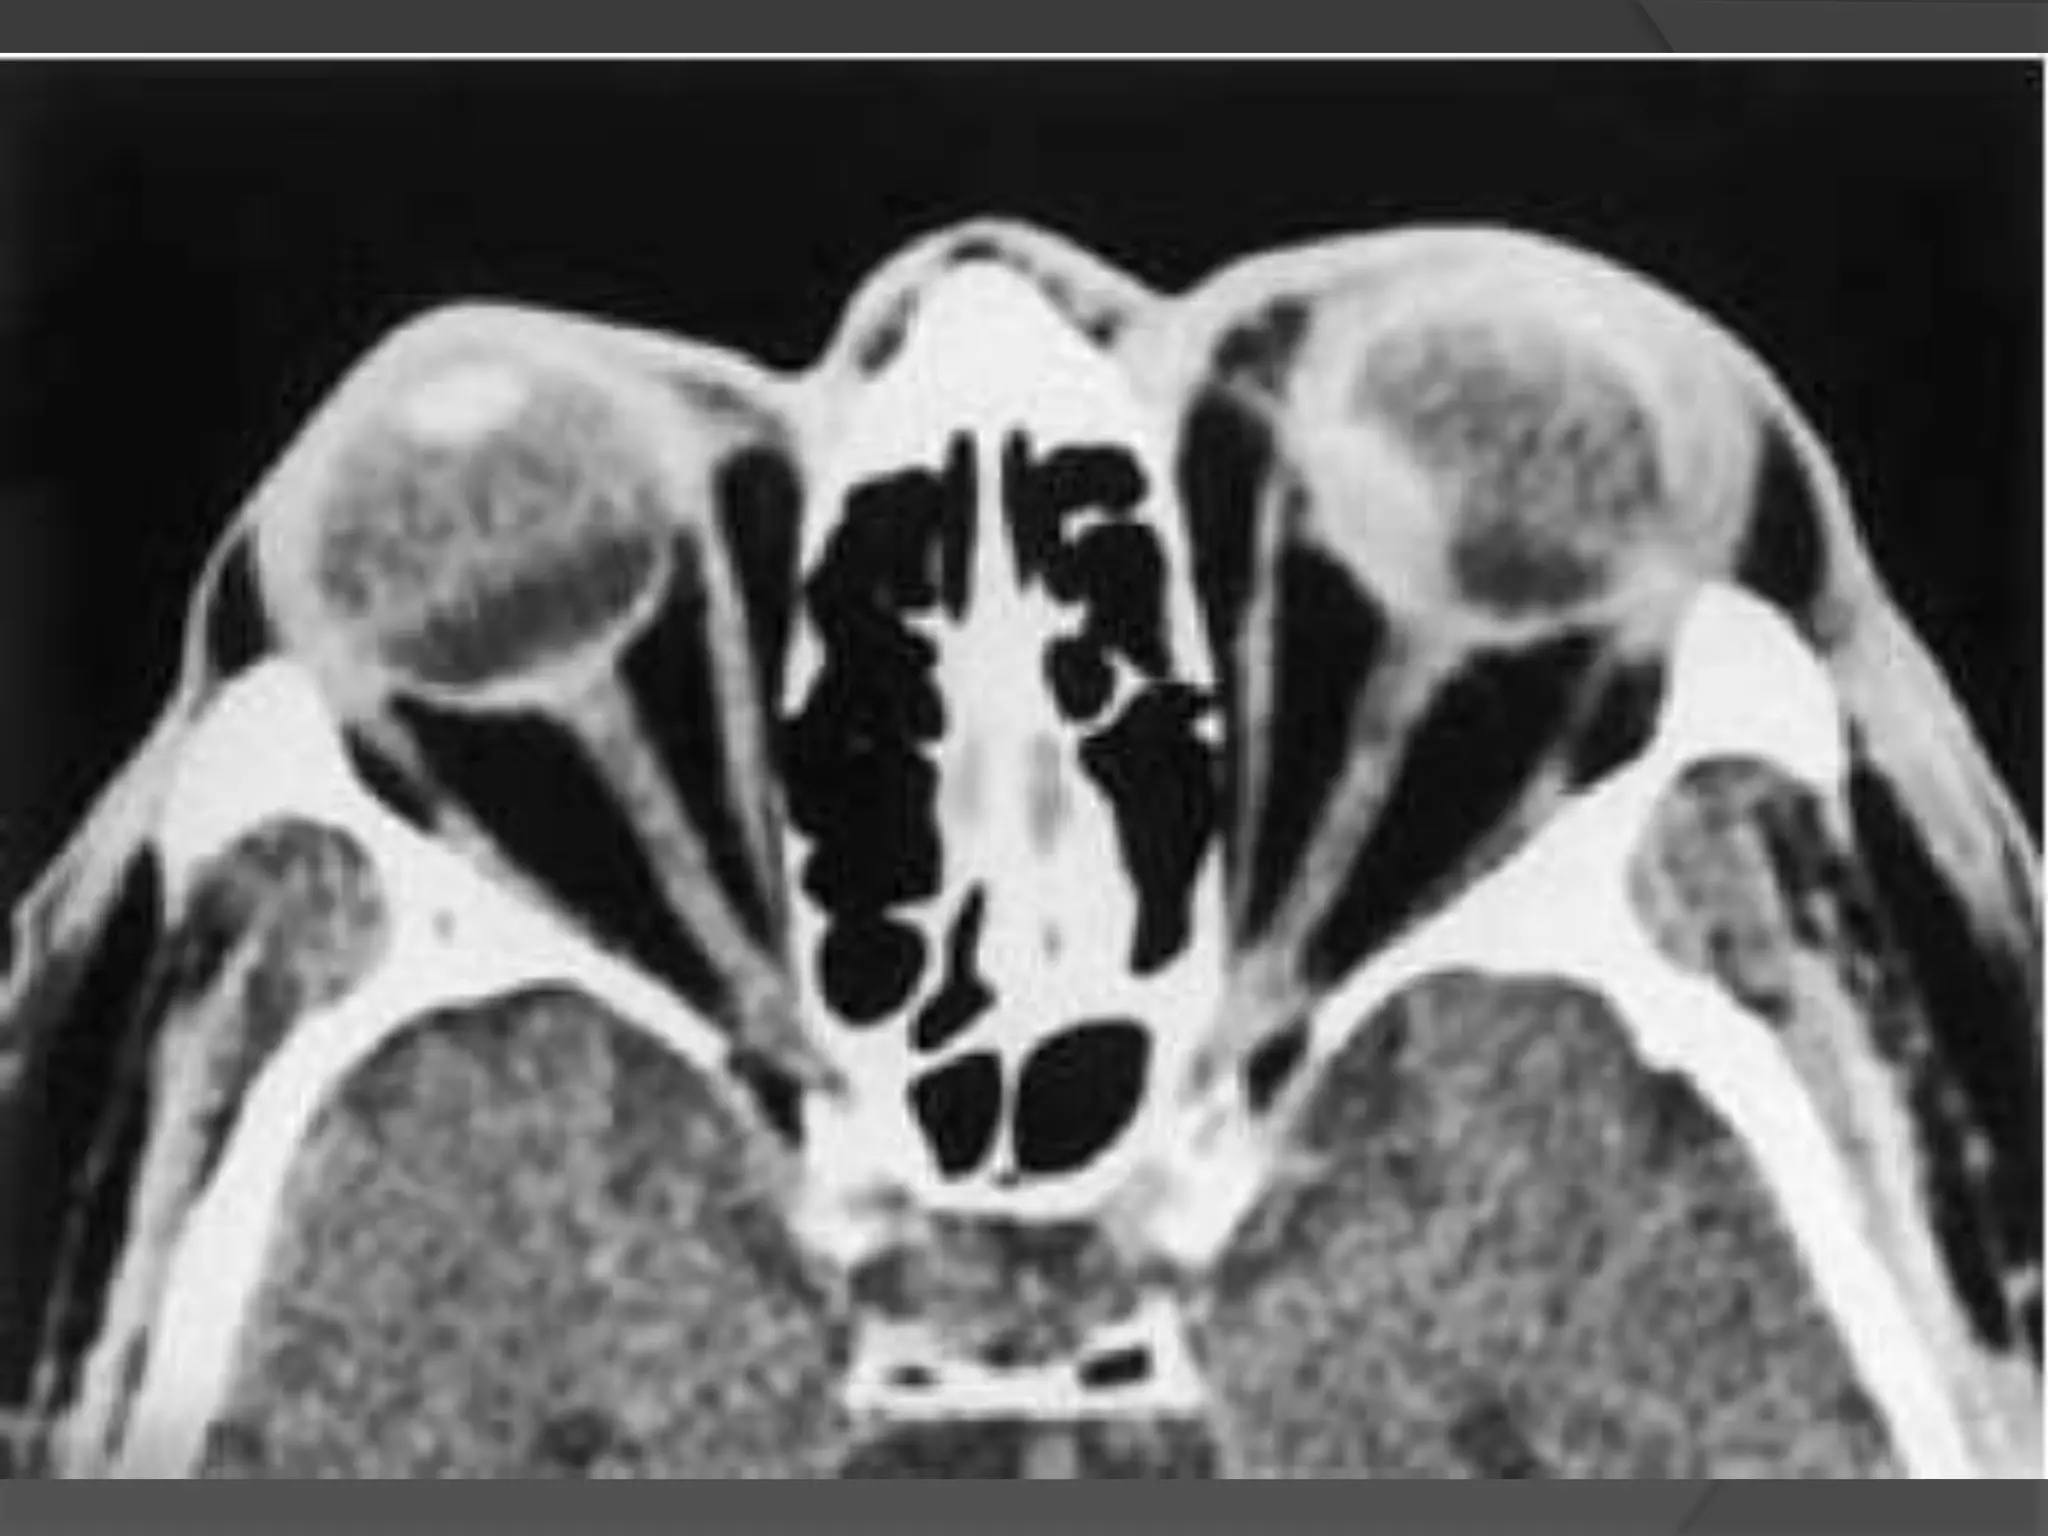

• #33 Coats’ disease. A, Axial CT scan shows generalized increased density of the left globe caused by bullous retinal detachment. The leaves of the detached retina are faintly seen, as shown by the arrows. B, Axial PW MR image shows hyperintensity of the left globe caused by subretinal lipoproteinaceous effusion. Note the leaves of the detached retina (arrows). C, Axial T2-weighted MR image shows the detached retina (arrows).